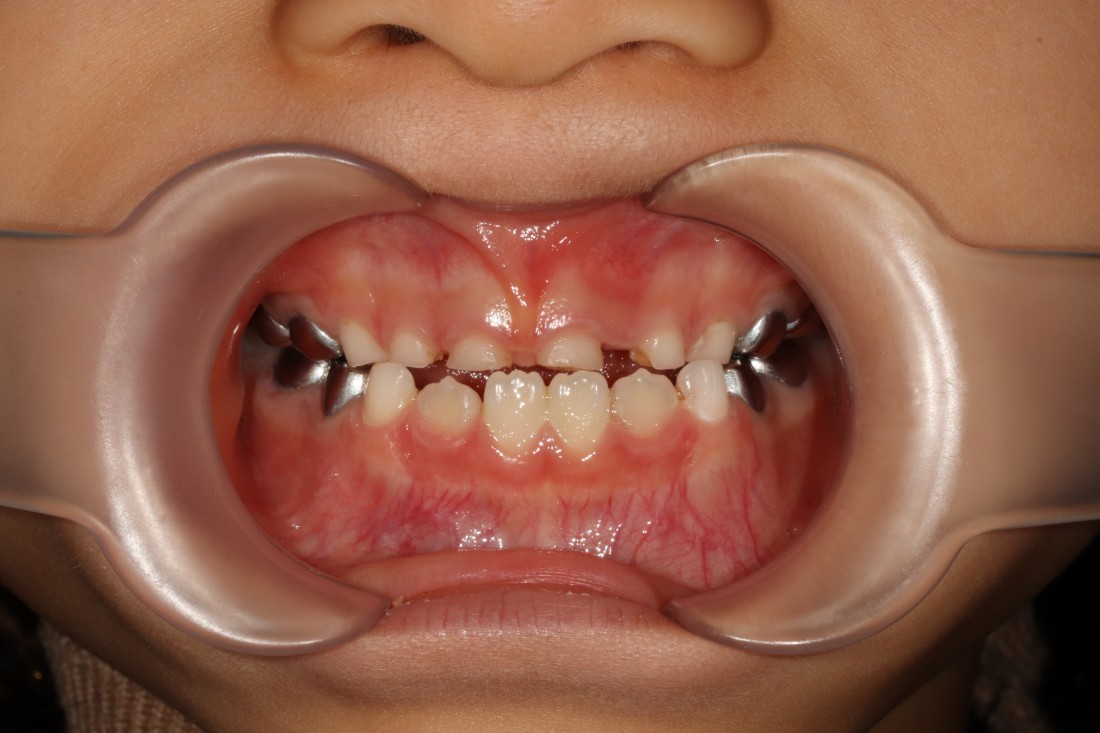

소아부정교합 중에서

반대교합의 경우에는

정상교합에 비하여

아랫니, 아래턱이 많이 튀어나와 있어

부모님들께서도 조기에 발견하실 수 있는데요.